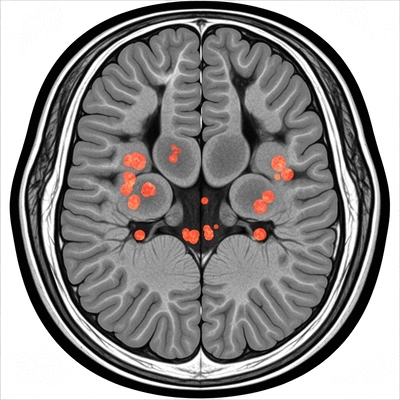

In the context of MS, an MRI detects lesions—areas of damage in the nervous system. These lesions occur due to the immune system mistakenly attacking the protective covering of nerves, known as myelin. By identifying these lesions, neurologists can distinguish MS from other conditions with similar symptoms, such as migraines or stroke. Research, such as that published in Nature Communications, consistently highlights the advanced capabilities of MRI in detecting these subtle changes early on.

Detailed MRI scan of a brain highlighting MS lesions

How MRI Detects MS Lesions and Differentiates Conditions